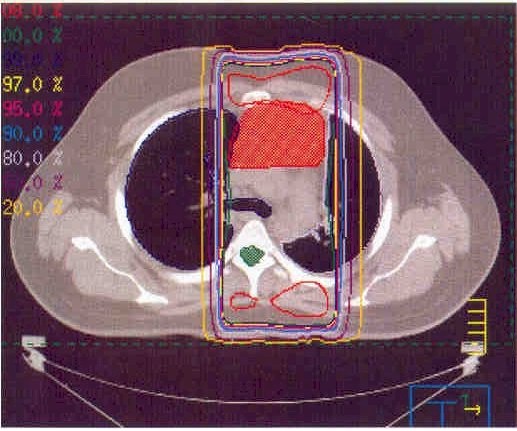

these are CT scan pictures and x-rays shoing the location of my tumor, it's current size, and the area that will be getting radiation therapy...

the bright red/orange solid area in the above pictures is my tumor.  the red outlined areas are where they are aiming the radiation through.